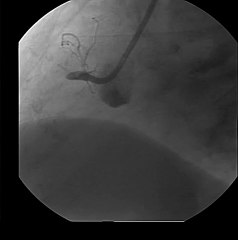

RCA TP003R Saio Wie, 50f Review

BRCA TP003R Saio Wie, 50f ReviewbP PP RCA TP003R Saio Wie, 50f PIvoryP